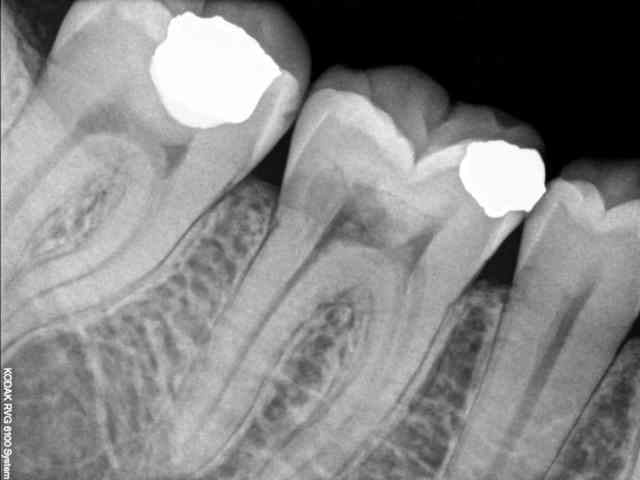

j'ai un patient qui vient en consultation pour ce que je croyait n'être qu'une simple mylolyse. douleur lors du brossage, petits chocs éléctriques, ...mais aussi douleur avec le sucre (inhabituel pour les mylolyses).

en regardant, je ne vois rien,et pas de mylolyse.

je fais une radio, et là.! voici ce qu'on trouve; une jolie cavité dans laquelle la sonde pénètre bien facilement.

Si ça se trouve, ce n'est pas une carie, mais une résorption externe. Il est possible qu'elle communique avec la pulpe, donc, on connaît la suite.

Le pb n'est pas de savoir avec quoi restaurer, le pb est d'abord d'apprécier l'étendue de la lésion et d'en tirer les conséquences.